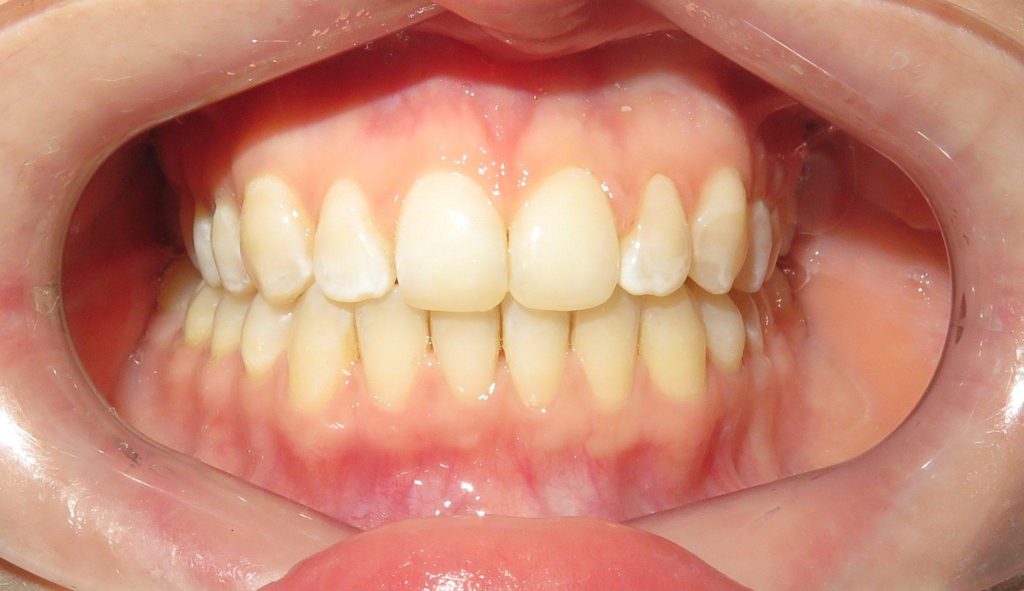

Dzięki precyzyjnej diagnostyce, doktor Magdalena Zawirska opracowała kompleksowy plan leczenia, który obejmował: stomatologię zachowawczą, periodontologię i protetykę stomatologiczną. Zastosowano licówki i korony pełnoceramiczne, przeprowadzając kompleksową rekonstrukcję zwarcia.

Pacjentka może się teraz cieszyć się pięknym i zdrowym uśmiechem